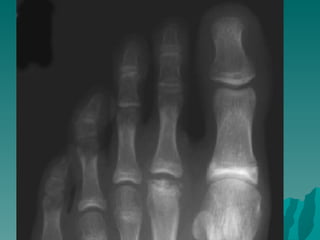

Freiberg Hastalığı:

 Metatars başlarının osteokondrozudur. En

çok ikinci metatars başında görülür.

Bilateral olabilir. %75 oranında kızlarda ve

adolesan çağda görülür.

 Hastalık metatarsaljiye neden olur.

hareket kısıtlılığı olur.

 Radyolojik olarak metatars başında

yassılaşma, düzensizlik ve skleroz görülür.

 Ağrılı dönemde alçı yapılır daha sonra

ayakkabının içine metatars yastığı

uygulanır.

 yakınmalar sürüyorsa, metatars başı

rezeke edilebilir.

Freiberg Hastalığı:  Metatarsbaşlarının osteokondrozudur. En çok ikinci metatars başında görülür. Bilateral olabilir. %75 oranında kızlarda ve adolesan çağda görülür.  Hastalık metatarsaljiye neden olur. hareket kısıtlılığı olur.  Radyolojik olarak metatars başında yassılaşma, düzensizlik ve skleroz görülür.  Ağrılı dönemde alçı yapılır daha sonra ayakkabının içine metatars yastığı uygulanır.  yakınmalar sürüyorsa, metatars başı rezeke edilebilir.